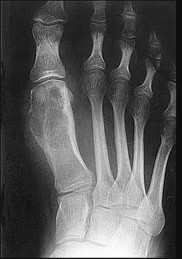

What is the diagnosis?

This patient has a dedifferentiated liposarcoma within a preexisting atypical lipomatous tumor. The imaging demonstrates a large fatty mass with increased internal septations proximally (the atypical lipomatous tumor) and a solid enhancing mass distally (the dedifferentiated portion). A biopsy reveals a high-grade liposarcoma. The other diagnostic responses do not reflect sarcomatous transformation of the lesion.